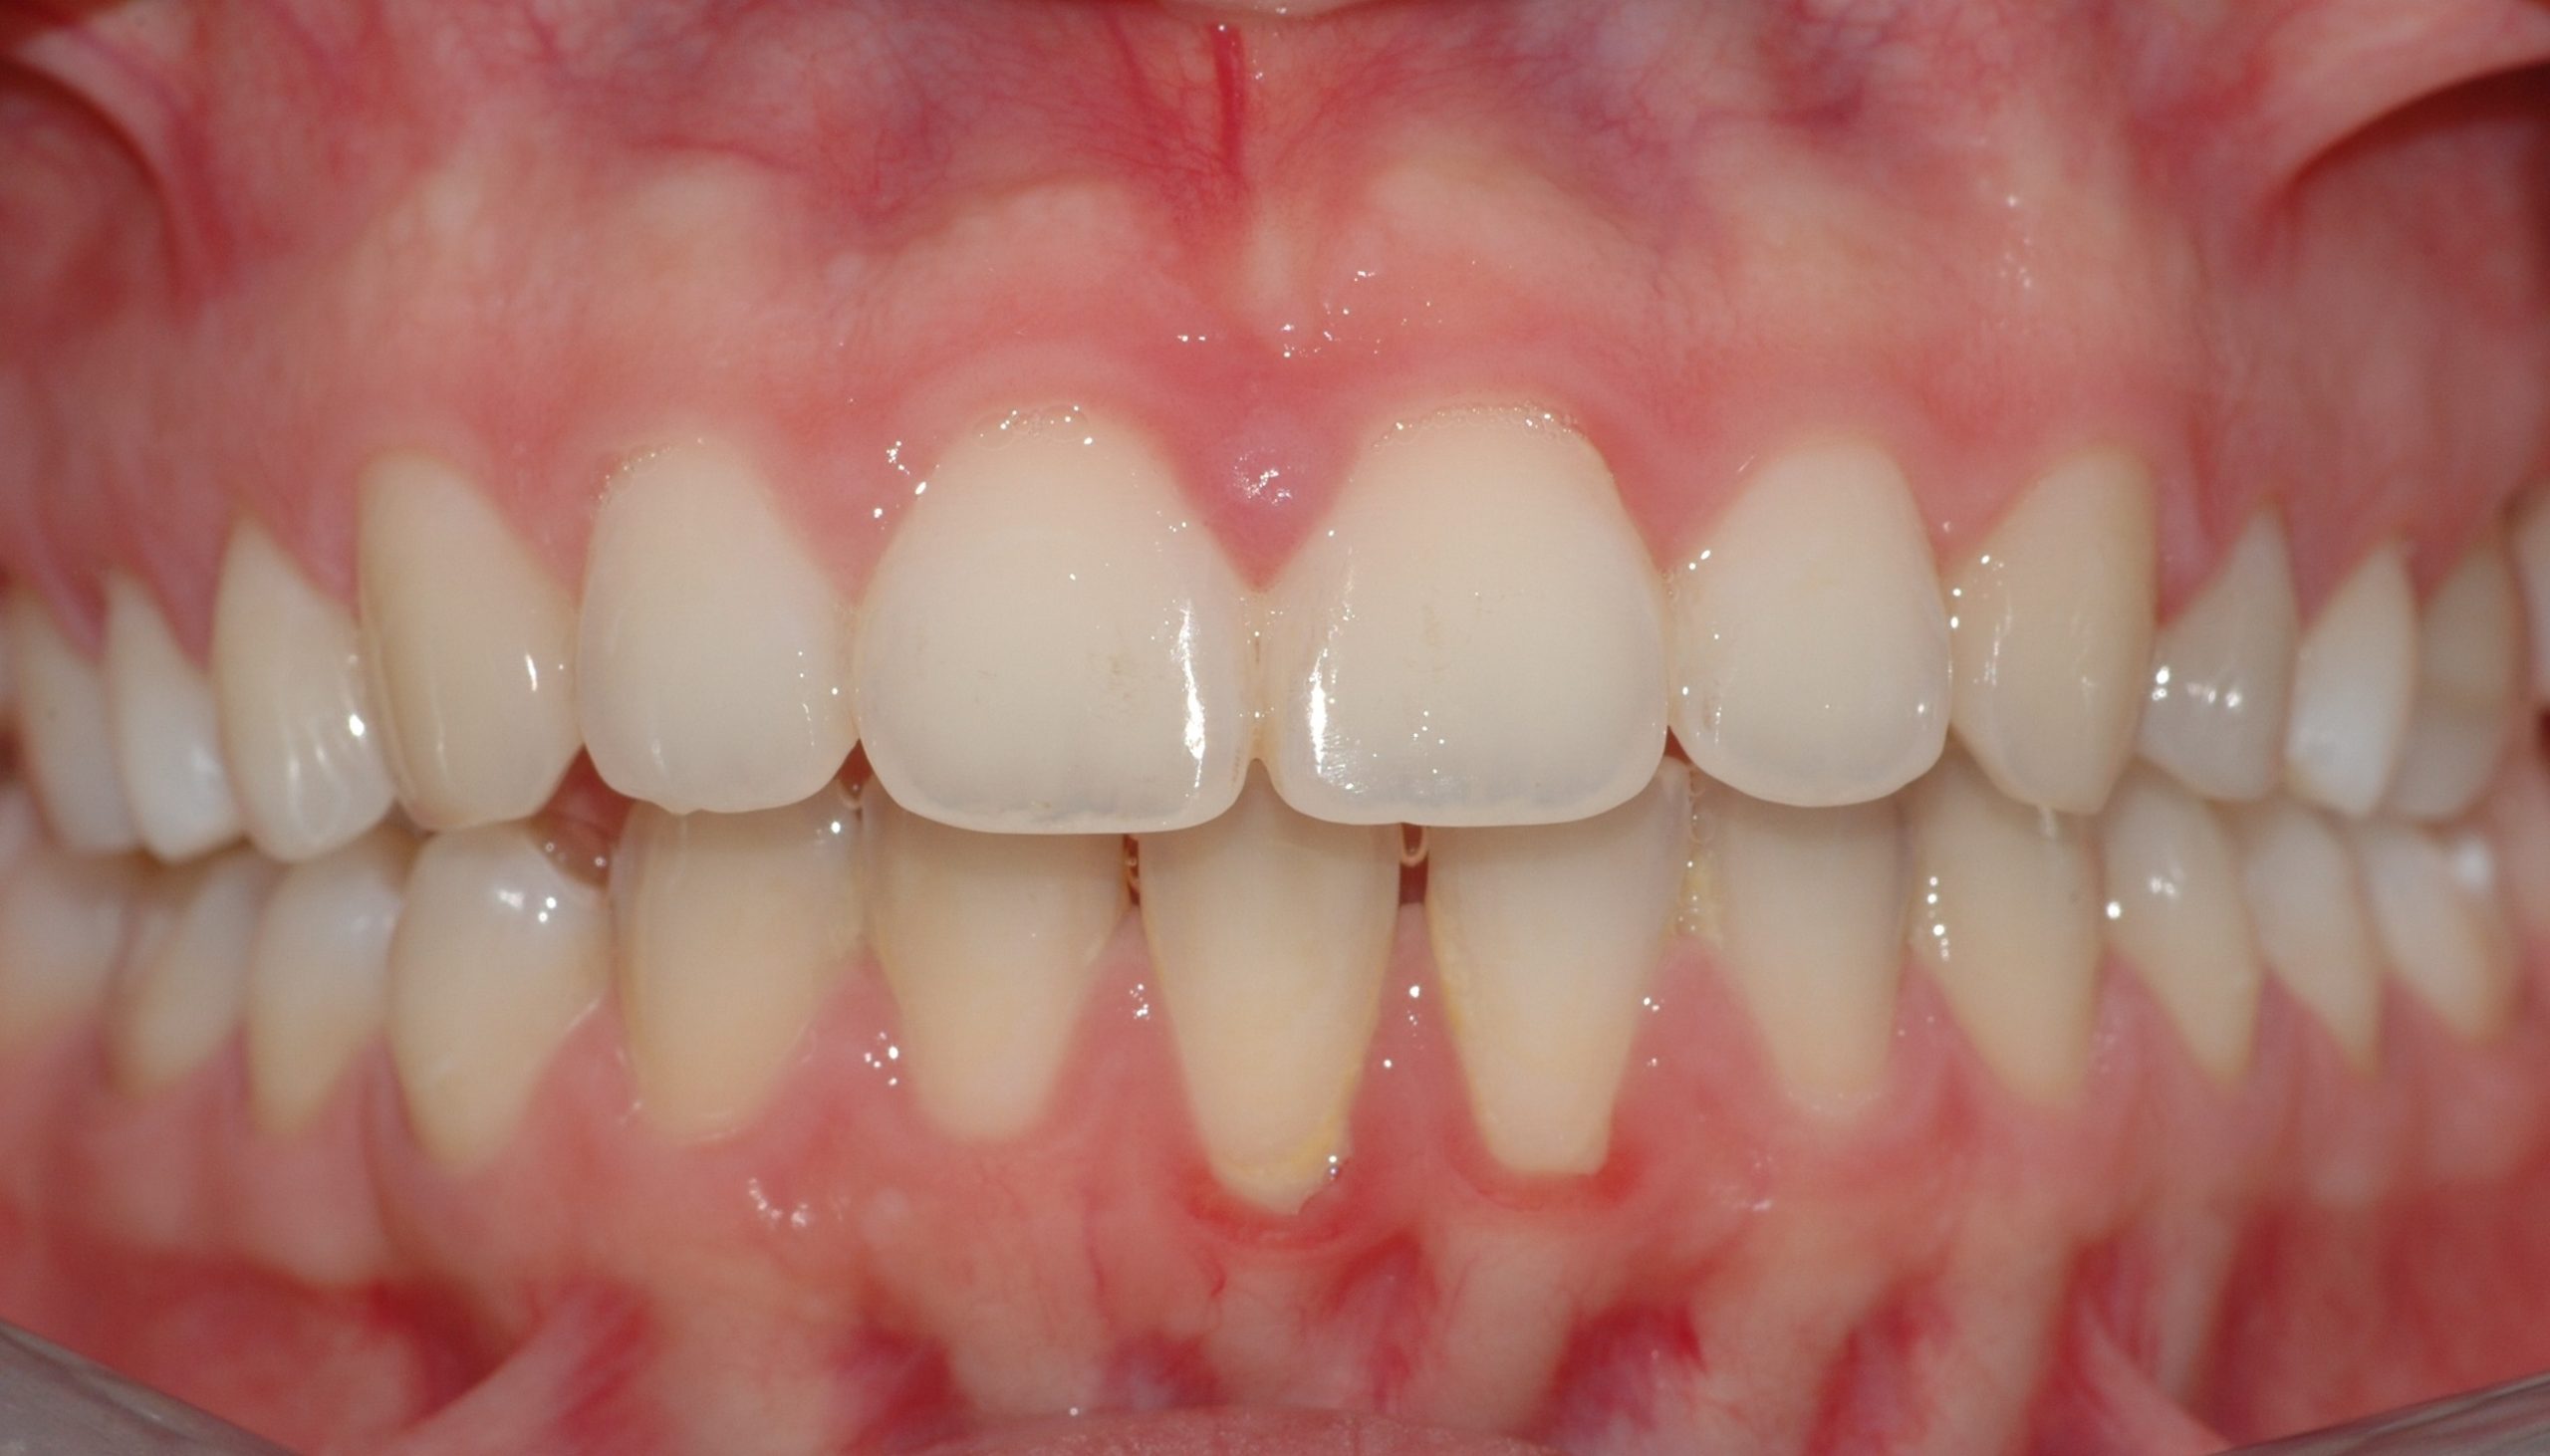

Caso clinico

La paziente presenta malposizione degli incisivi antero-superiori, in particolare un forte sventagliamento degli incisivi laterali. In seguito a trattamento con allineatori trasparenti, durato 9 mesi, si è ottenuto un allineamento pienamente soddisfacente.

PRIMA

DOPO